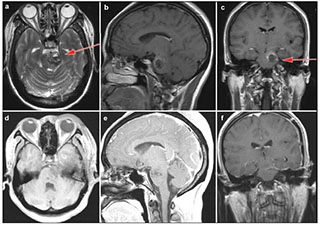

Case 2: A 40-year-old man was admitted to hospital because of right hemibody weakness (4/5), mRS 2. He was found to have a left anterolateral medullary hemorrhage as a result of underlying CM (Figure 4). A left retrosigmoid approach was applied to gain access to the lateral medulla oblongata, where the cavernous malformation was observed to come to the surface. When he was discharged, the right hemibody weakness (3/5) was slightly worsened. At 5 months' follow up, the patient had completely recovered and returned to work, mRS 0.

| Figure 4 Case 2: Left anterolateral medullary cavernous malformation. Axial T2-weighted (a) and sagital T1-weighted (b) showed the location of the lesion. Axial T1-weighed (c) and enhanced sagittal T1-weighted (d) postoperative within 72 h showed that the lesion was totally resected. Enhanced axial T1-weighted (e) and enhanced sagittal T1-weighted (f) at 5-month postoperative follow-up. Red arrow showed the entry approach (retrosigmoid approach). |

Case 3: A 30-year-old woman developed acute onset of headache, right hemibody weakness (4/5), mRS 2. Because of her CM located in the left pons and lower midbrain, a left subtemporal approach was performed (Figure 5). She developed slightly worsening of her right hemibody weakness (3/5) postoperatively. At 2 months' follow up, the patient had improved her right hemibody weakness, mRS 1.

| Figure 5 Case 3: Cavernous malformation in the left pons and lower midbrain. T2-weighted (a), enhanced sagittal T1-weighted (b) and enhanced coronal T1-weighted (c) demonstrated the location of the cavernous malformation. Enhanced axial T1-weighted (d) and sagittal T1-weighted (e) postoperative within 72 hours showed that the lesion was totally resected. Enhanced coronal T1-weighted (f) showed no recurrence after 3 months follow-up. Red arrow showed the entry approach (subtemporal approach). |